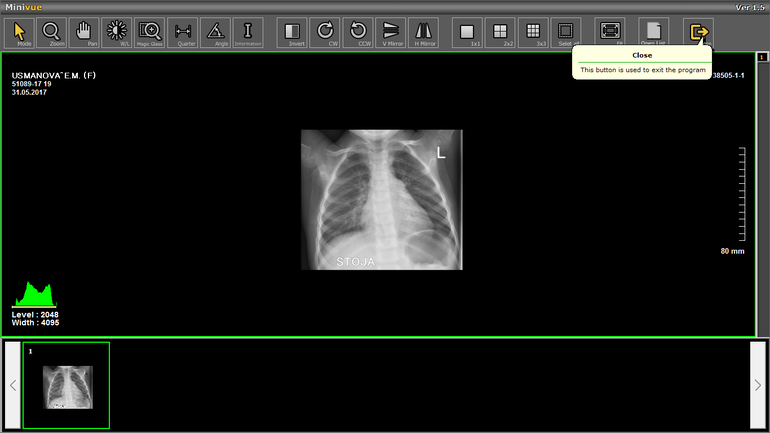

Снимки от 26 мая и 31 мая

С 28 апреля был бронхит. 12 мая поставили пневмонию, уколы и т. д. динамика была все хуже, скопилась жидкость в легких. Легли 22 мая в Морозовскую больницу, жидкость ушла при лечении. И врач сказал что есть положительная динамика по снимкам, отдали на руки диски и выписали. Я дома открыла и не пойму что дальше делать. Дочь опять стала кашлять сильно, отхаркивая, температура 37,5 держится постоянно. Нам назначили просто пить Амбробене. Сказали что после пневмонии температура это нормально. Неужели лечение завершено? Кровь завтра идем сдавать по месту жительства. Антибиотики Цифипим в капельницах и Суммамед 5 дней в больнице были. Есть у нас тут детские доктора, помогите, направьте пожалуйста.